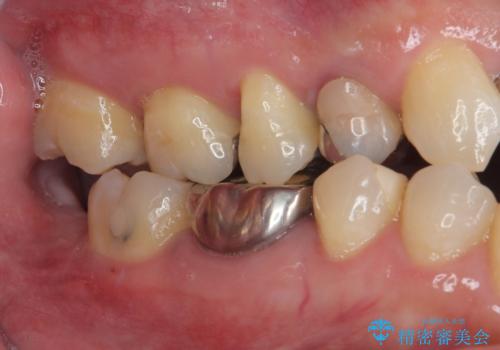

- 適合の良くない銀の詰め物が入っており、白い詰め物へのやり替えをご希望された患者様です。

メタルインレーを除去したところ、虫歯ができていたため取り除いたうえでハイブリッドインレー修復を行いました。

Ⅲ級咬合の患者さまで、奥歯への負荷が強いため、セラミックよりも破損のリスクが低いハイブリッドインレー治療を行いました。